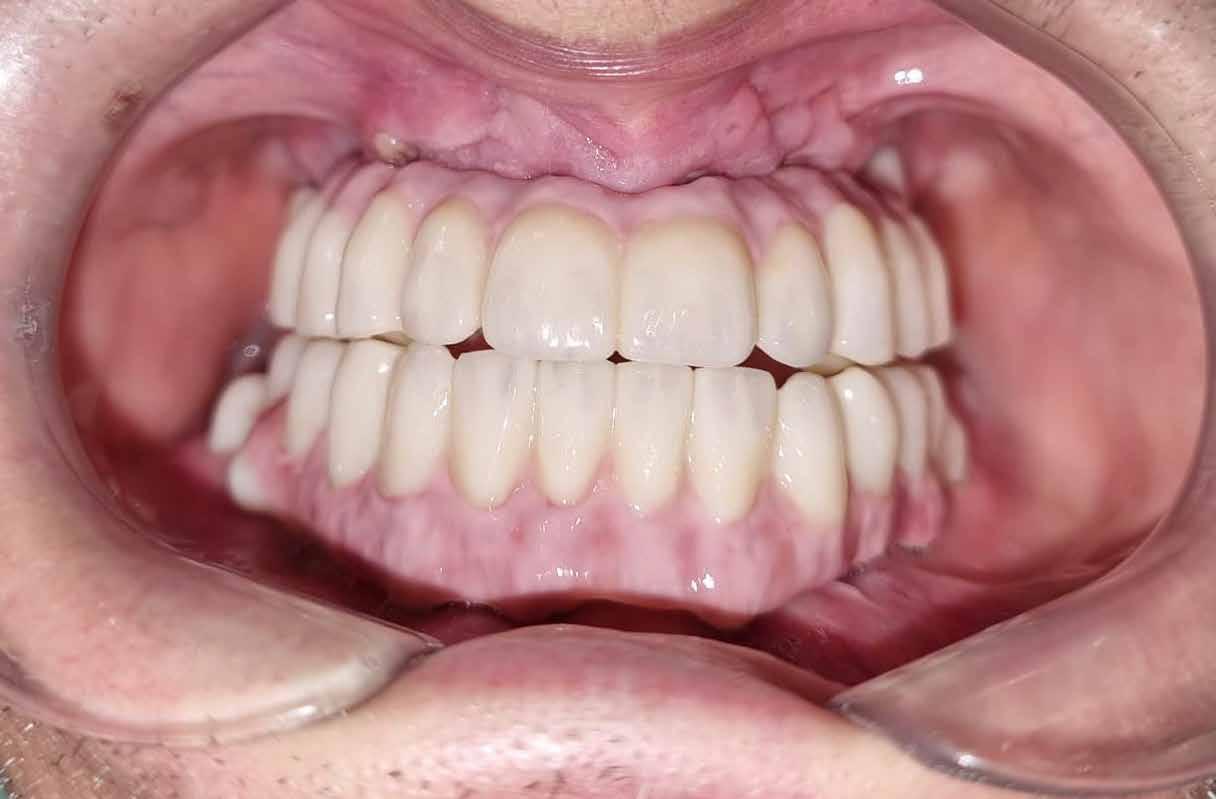

Az alábbi – négy esetből álló – sorozatban a CERALOG rendszert (BioHorizons Camlog) alkalmaztuk, és szóló foghiányok kerültek ellátásra. A CERALOG implantátumok Y-TZP-ből készülnek (10). A CERALOG rendszer minden szükséges elemet biztosít ahhoz, hogy bármilyen típusú pótlás megtartását lehetővé tegye ezeken az implantátumokon, az egyedi koronáktól a teljes ívre kiterjedő pótlásokig.

Az alábbi esettanulmányhoz négy pácienst választottunk ki (1. táblázat). Minden esetben egy, vagy több fog pótlására volt szükség, amelyhez kerámiaimplantátumokat használtunk. Valamennyi páciens általános egészségügyi állapota jó volt.

A sebészeti eljárás

Mind a hat implantátum esetén kétlépcsős műtétet végeztünk. Minden sebészeti eljárást bódítás, illetve preoperatív szisztémás antibiotikus terápia nélkül végeztünk. A négy eset közül kettőnél leukocitában és vérlemezkében gazdag fibrint (L-PRF) alkalmaztunk a beavatkozás során (IntraSpin, BioHorizons; 2. táblázat). Minden esetben a pontos CERALOG menetvágási (maximum 15 ford./perc) és fúrási (maximális fúrási fordulatszám: 550–800 ford./perc) protokollt követtük. Az összes implantátumot manuálisan helyeztük be 35 Ncm maximális nyomatékkal. Az implantátumokba PEEK zárócsavar került (2. ábra). A lágyszövetet atraumatikus, felszívódó varrattal, szorosan zártuk/összevarrtuk. A műtétek után szövődmények nem jelentkeztek. A pácienseket arra kértük, hogy a műtét utáni héten naponta kétszer öblögessenek klórhexidinnel (PERIO-AID, 0,05%, DENTAID). Az alsó állcsontnál három hónapos, a felső állcsontnál öt hónapos gyógyulási időt vettünk figyelembe. Három hónap (1. eset) és öt hónap (2., 3. és 4. eset) elteltével a műtétek második stádiumát helyi érzéstelenítés mellett végeztük. A gyógyu-

lási csavarokat (PEEK titáncsavarral) maximum 15 Ncm-rel húztuk meg (3–6. ábra). Az összes implantátum kiváló stabilitást mutatott (a mérésekhez Periotestet használtunk, a Medizintechnik Gulden jóvoltából), és teljesen osszeointegrálódott. Ezt a radiológiai vizsgálatok is megerősítették.

tottuk (az okklúziós koncepciók alapján az implantációs pótlások nem voltak vezető fogak, és csak könnyű érintkezéseket alakítottunk ki, amelyeket artikulációs papírral ellenőriztünk). A páciensek instrukciókat kaptak a megfelelő szájhigiénére vonatkozóan, összpontosítva a fogköz kefékkel történő tisztítására. Végső kontroll röntgenfelvétel készült. A PEEK felépítmény nem radioopák, így az implantátum és a korona közötti távolság könnyen meghatározható a röntgenfelvételen: a felépítmény megfelelően illeszkedik az implantátumban, ha az implantátum válla és a korona alsó széle közötti rés 0,55 mm a röntgenfelvételen (8–11. ábra)

Összegzés

Minden páciens elégedett volt a kezelés eredményével, a funkcionális és az esztétikai eredmény egyaránt kielégítő volt. Az egyetlen megjegyzés – a teljes kezelés hosszú időtartama – a felső állkapocs esetében volt. A meghosszabbított, öt hónapos csontintegrációs periódus miatt, a teljes

eljárás több mint hat hónapig tartott. A kezelő szemszögéből a gyártó szigorú előírásainak betartása mellett nem volt jelentős különbség a titánimplantátumok használatához képest. A felső és alsó állcsont fogainak pótlásában a CERALOG implantátumok megfelelő és stabil alternatívának tűnnek a titánimplantátumokkal szemben.